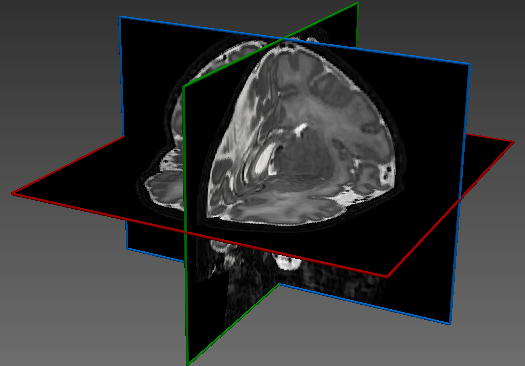

The dataset consisted of 70 3D T2-weighted brain MRI scans publicly available from the dHCP neonatal cohort. The segmentation maps had 10 classes, corresponding to: zero-pixel background, cerebrospinal fluid (CSF), cortical grey matter (cGM), white matter (WM), background bordering brain tissues, ventricles, cerebellum, deep grey matter (dGM), brainstem, and hippocampus. The scans covered an age range of 24.3-42.2 weeks. The data was available in NIfTI format; Figure 1 shows an example scan and corresponding tissue labels. We carried out a pre-processing step where each scan was independently normalised to zero-mean and unit-variance.